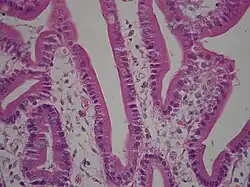

twaalfvingerige darm met borstelzoom (microvilli)

De borstelzoom is de homogene laag die aan de apicale zijde (de bovenkant/de naar de darmholte gerichte kant) van de absorberende cellen in de dunne darm, en van de epitheelcellen in de proximale tubulus (in de nieren) zichtbaar is. Als dit weefsel wordt bekeken onder een lichtmicroscoop, dan ziet men dat de borstelzoom bestaat uit een groot aantal dicht opeengepakte microvilli. Deze microvilli zorgen voor een 20-voudige vergroting van het darmoppervlak van de dunne darm. De oppervlaktevergroting vergemakkelijkt de opname van voedingsstoffen aanzienlijk.